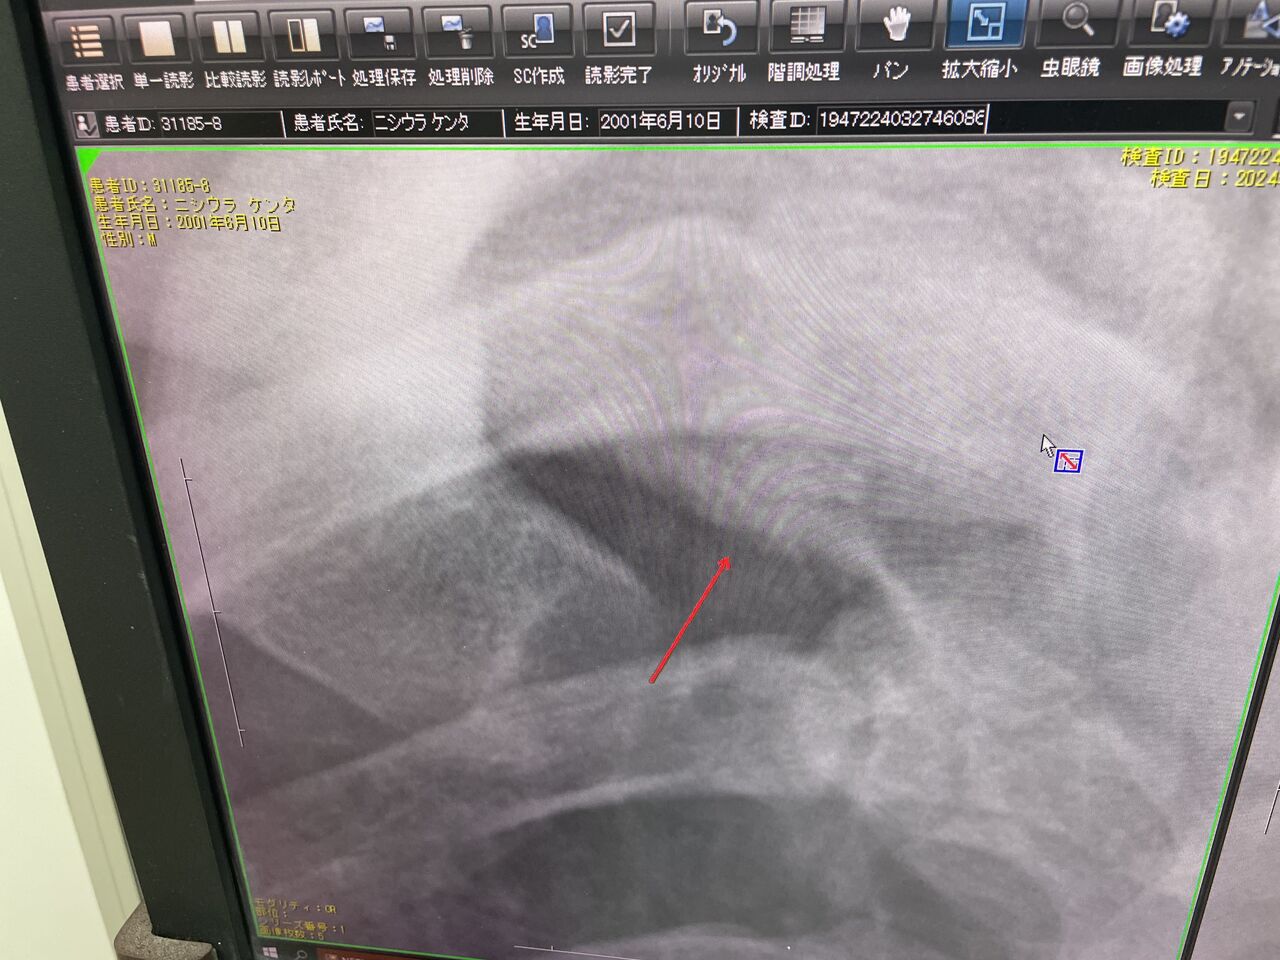

捕手選手が、エースのボールが、

右鎖骨に直撃、不全骨折になりました、

細かい骨折については、CTで、詳細な情報をつかんで

LIPUS、副甲状腺ホルモン等も、考えていきたい

と思います